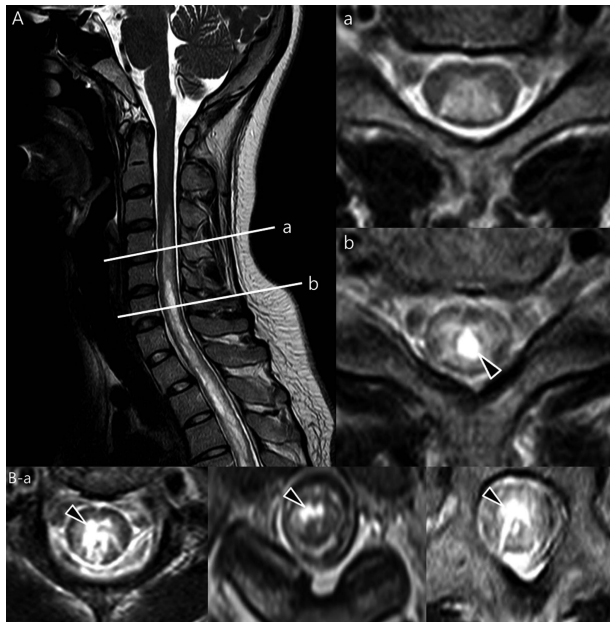

Q7: A 75-year-old woman with history of prior cervical spine decompression presented with progressive neck pain, asymmetric hand tingling, and neuropathic pain, followed by urinary incontinence and gait difficulty. Sagittal T2 weighted imaging likely shows?.